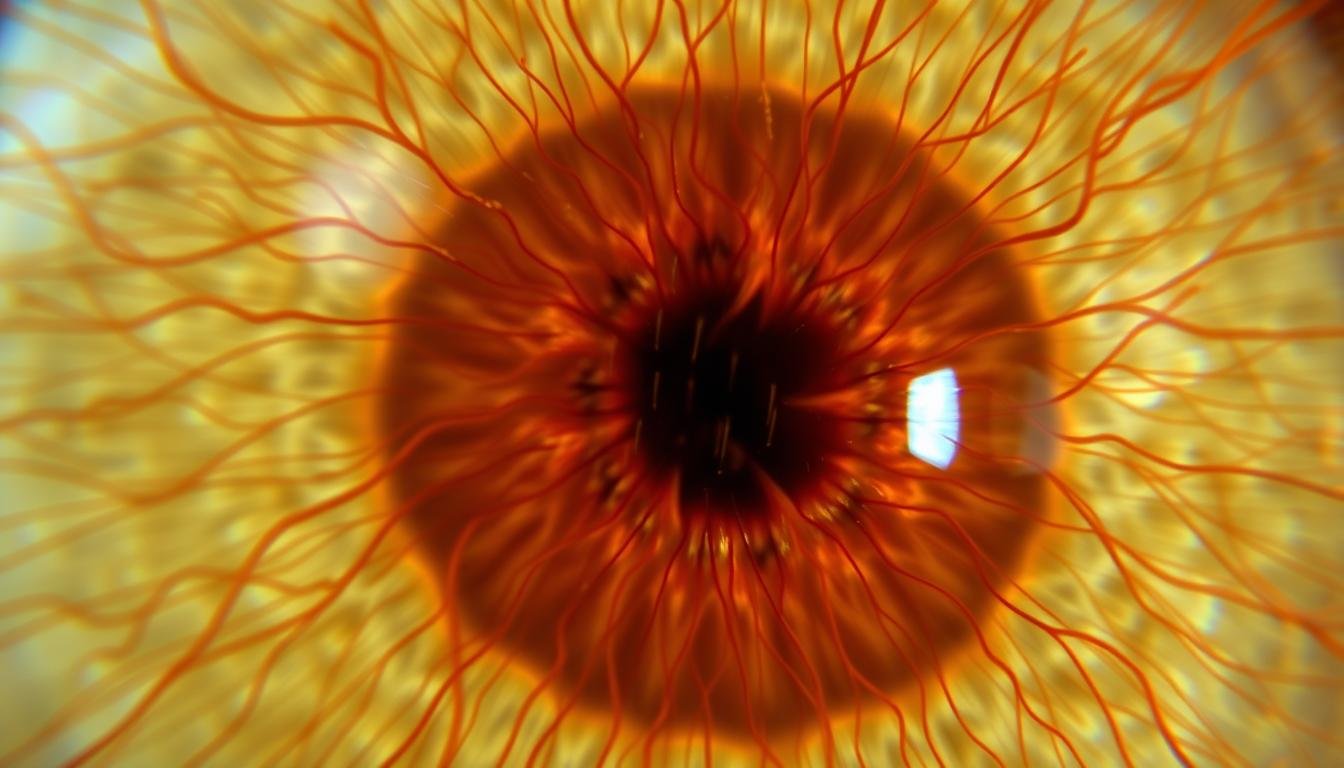

2. Microestructura única

Cada iris es único y contiene una microestructura compleja formada por fibras, criptas, anillos y otros elementos distintivos. Esta unicidad, similar a la de las huellas dactilares, permite identificar características individuales y patrones específicos que pueden correlacionarse con predisposiciones genéticas y estados de salud particulares.

Microscopía de alta resolución mostrando la compleja estructura del iris

Es importante señalar que, aunque estos principios tienen base científica, la interpretación específica de los signos del iris y su correlación con órganos particulares sigue siendo objeto de debate en la comunidad médica convencional. La investigación científica moderna continúa explorando las posibles correlaciones entre los patrones del iris y las condiciones de salud.

Los avances en tecnología de imagen han permitido documentar con mayor precisión los cambios en el iris a lo largo del tiempo, proporcionando datos más objetivos para el análisis. Estos avances están contribuyendo a un enfoque más riguroso y basado en evidencia para la lectura del iris.